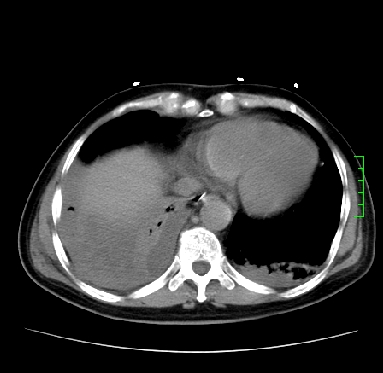

icu病人,几天都没明确诊断。m,76y,咳嗽、咳痰1周,伴气促,右胸痛入院,pe:t38.3c p135 r25 bp135/85。双肺可闻及大量湿罗音,心、腹未见明显异常。诊断:1心衰?2肺部感染?3冠心病?

11号ct